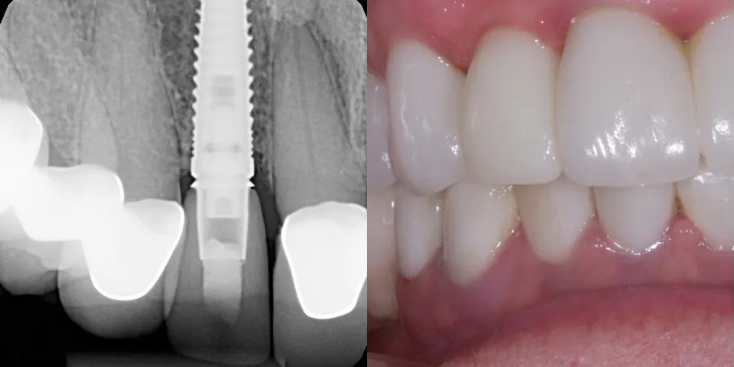

Before Treatment

After Treatment